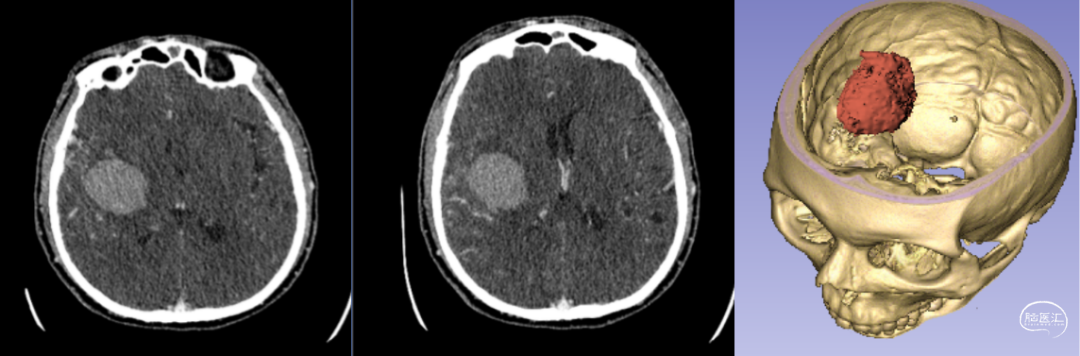

新疆醫(yī)科大學第一附屬醫(yī)院神經外科中心已成功將該技術應用于多例腦卒中患者的治療。以一例典型病例為例:[14]

- 患者情況:52歲女性,因“右側肢體無力1天”就診,入院時呈淺昏迷狀態(tài),雙側瞳孔等大等圓(直徑約3.5mm),對光反射遲鈍,右側肢體肌力為0級。

- 手術過程:基于術前影像數據,團隊利用3D打印技術設計并制作個性化手術導板,精準定位血腫位置后實施穿刺引流。術后復查頭部CT顯示,引流管準確位于血腫腔內,血腫清除效果良好。